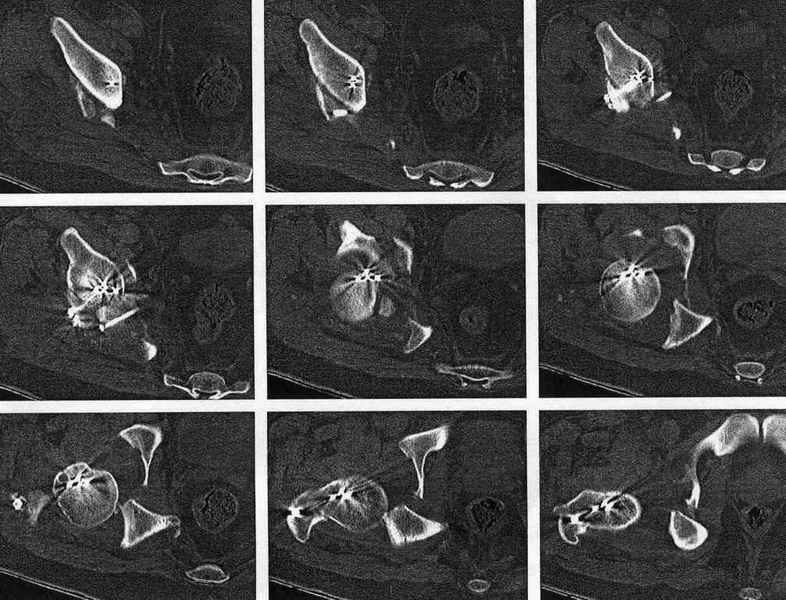

XrayCTРезультат повторной операции

Большое спасибо всем коллегам ответившим на моё сообщение (Ацетабулярный перелом). С чувством глубокого удовлетворения должен вам сообщить что телеконсультации привели к конкретному результату: нам любезно предоставили свою помощь специалисты из Республиканского центра повреждений таза г.Екатеринбург.

В нашей клинике 23.04.03 руководитель центра А.В. Рунков выполнил выездную показательную операцию. Не смотря на то, что с момента травмы прошло 2 месяца отломки вертлужной впадины были репонированы, восстановлена конгруэнтность суставных поверхностей тазобедренного сустава, фиксация реконструктивной пластиной. Операция была выполнена на высочайшем профессиональном уровне и её результат превзошёл мои ожидания.Ранний послеоперационный период протекает без осложнений, больной "воспрял духом", чувствует себя хорошо, занимается ЛФК, разработкой движений в коленном и тазобедренном суставах, сидит, ходит на костылях. На мой взгляд представленный случай является ярким примером целесообразности телеконференций, позволяющим достичь конкретного результата. Особую благодарность хочется выразить Александру Челнокову - организатору Форума. С Уважением Андрей Стасюк